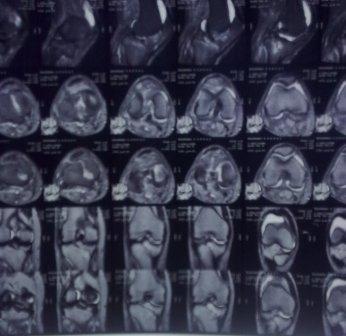

Здравствуйте уважаемые коллеги!Сегодня обратился больной 35л. Травму получил 3 мес.назад, упал в яму, лечился в отдаленном районе гипсовой повязкой, 1 месяц назад гипс сняли , и больной начал ходить с нагрузкой, постепенно появилась деформация коленного сустава, неустойчивость и боли. Локально: деформация коленного сустава, голень смещена кзади- типа подвывиха, разгибание 170гр. Сгибание 150гр.симптомов повреждение коллатеральных и крестообразных связок определить не удается из-за боли и контрактуры. Первичных снимков пока нет, обещали принести, имеется снимки через 2 месяца после травмы без гипса, недельной давности снимки в прямой проекции и К Т. Похоже, что импрессия переднемедиальной части внутреннего мыщелка б/берцовой кости, отрыв межмыщелкового возвышения.

Оперировать нужно,наверно после разработки-проведение остеотомии большеберцовой кости.Да, Вы так же думаете.Я бы,1-ым этапом, провел санацию коленного сустава-возможно мешает поврежденный наружный мениск,это можно сделать и сразу,не ожидая восстановления объема движений,конечно лучше артроскопом.Дообследования о возможном характере внутрисуставных повреждений(УЗИ,ЯМРТ)я понимаю не проведено.Есть возможность?-Сделайте,проще будет планировать вмешательство.

На снимке типичный перелом медиального тибиал плато с передним смещением (подвывих) по Schatzker IV. Консервативное лечение без медиальной опоры не может удержать деформирующие силы, и из-за вторичного смещения мыщелка конечность смещается в варус. Кроме передних смещений еще встречаются сложные фронтальные варианты переломов, и тогда голень подвывихивается кпереди.

А в данном случае мыщелок сросся со смещением кпереди и ротирован. За счет интактной наружной колонны опороспособность конечности сохранена, но остается варус и экстензия конечности. Для предоперационного расчета необходимо сделать на всю длину конечности рентгенограмму, а в остром периоде КТ и 3-мерный снимок помогут лучше ориентироваться в характере перелома.

Остеотомия с разворотом медиального мыщелка, и для фиксации можно применить параллельные субхондральные межмыщелковые шурупы. Дополнительная медиальная Smith-Nephew PERI-LOC™ (Periarticular Locked Plating System) пластина. При отсутствии специальной пластины можно адаптировать Tomofix для высокой остеотомии. Доступ прямой медиальный через pes anserinus или через интервал pes с medial gastrocnemeus.